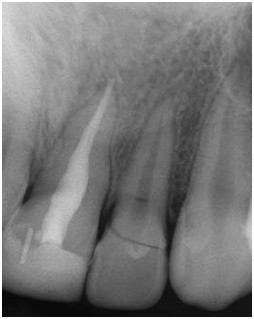

Wskaż fałszywe stwierdzenie dotyczące ujść kanałów zaprezentowanych na poniższej rycinie: